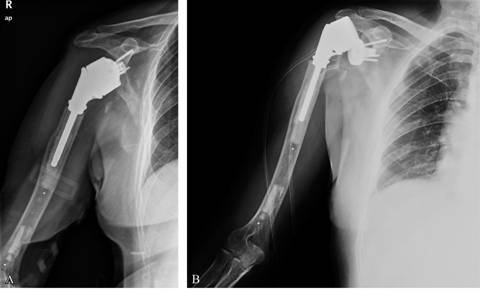

Seis días después de la misma, el paciente presentó un primer episodio de luxación de manera espontánea, sin trauma asociado (Figura 2). Se redujo en quirófano de manera cerrada con sedación y una buena estabilidad. Otro episodio de luxación atraumática ocurrió en los días siguientes. Finalmente tras un tercer episodio en el cual fue necesario recurrir a una reducción abierta, otra vez con buena estabilidad tras la reducción, se decidió realizar una cirugía de revisión, implantando componentes que aportaron mayor estabilidad. (LIMA SMR Total Shoulder Replacement System: 80 x 7 mm vástago tumoral) (Figura 3A).

Figura 3: A) Segunda cirugía de revisión. B) Flexión de hombro después de todos los tratamientos quirúrgicos y tres años de evolución.

Hasta el día de hoy, tras 37 meses la analítica se mantiene normalizada, el paciente ha vuelto a desempeñar su trabajo y actividades diarias sin limitaciones y tiene un rango de movilidad de 150o de elevación, rotación interna hasta L4 y rotación externa muy poco limitada (Figura 3B).